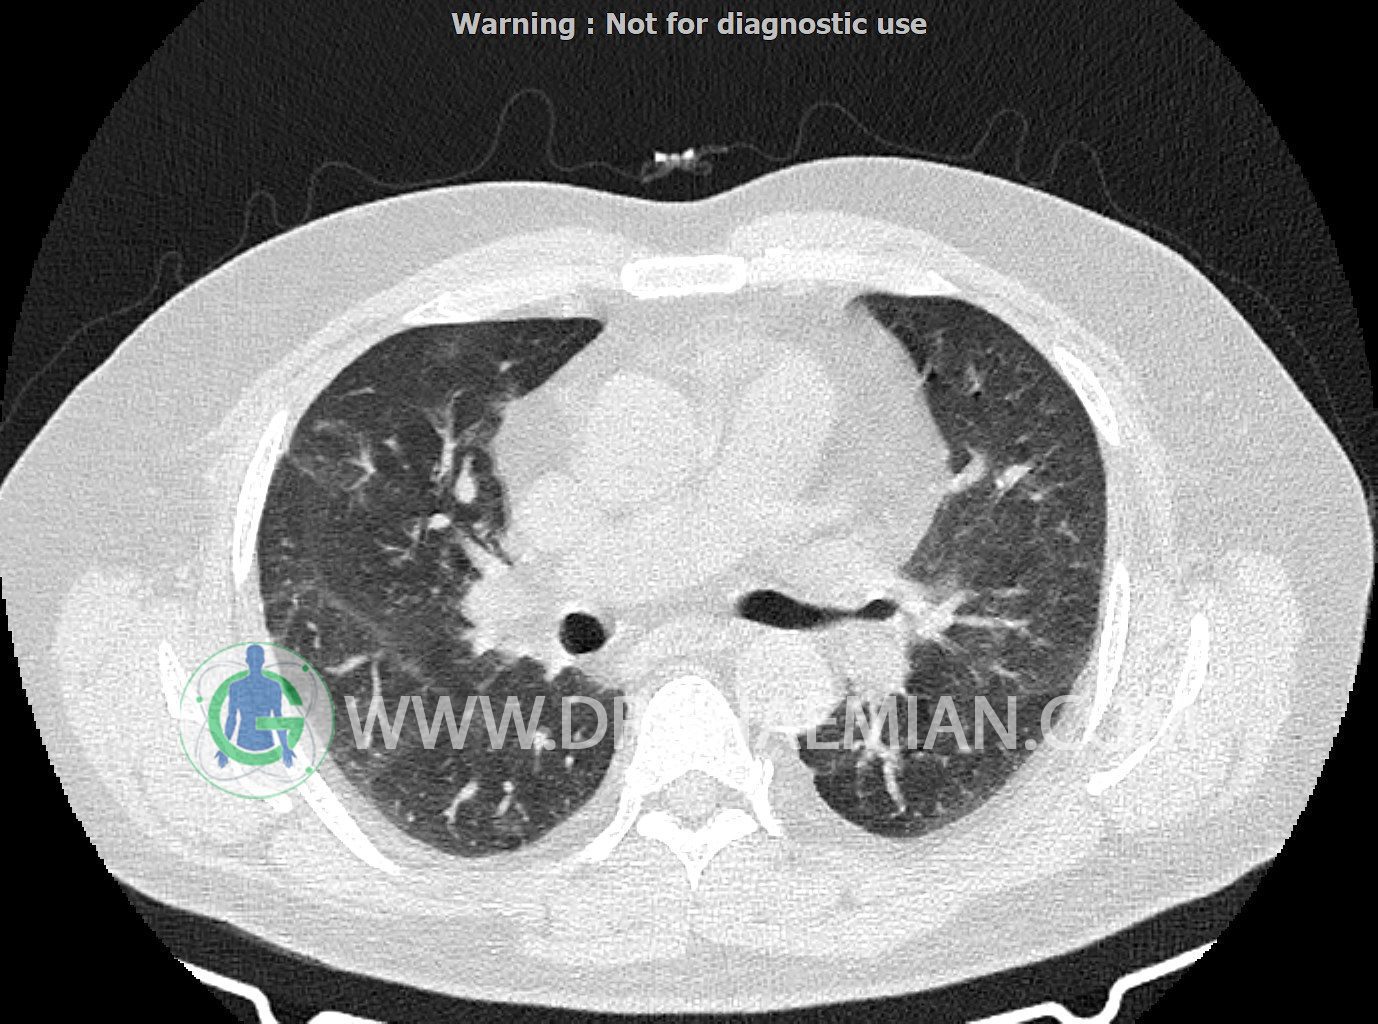

سی تی اسکن ریه یک روش تصویربرداری است که با استفاده از تشعشعات تصاویر عرضی مقطعی از ریه و بالا تنه ایجاد می کند. در این کیس کاردیومگالی،باندهای آتلکتازی و فیبروتیک پراکنده،کدورت های گراند گلاس،زمینه ی ادم قلبی (مراحل اولیه)،مشهده میشود.

smooth septal thickening در لوب فوقانی ریه ها

peribronchial wall-thickening و عروق prominant در هیلوم دو طرف و کدورت های گراند گلاس دو طرفه

مشهود است.

شواهد فوق در درجه اول می تواند در زمینه ی ادم قلبی (مراحل اولیه) باشد.